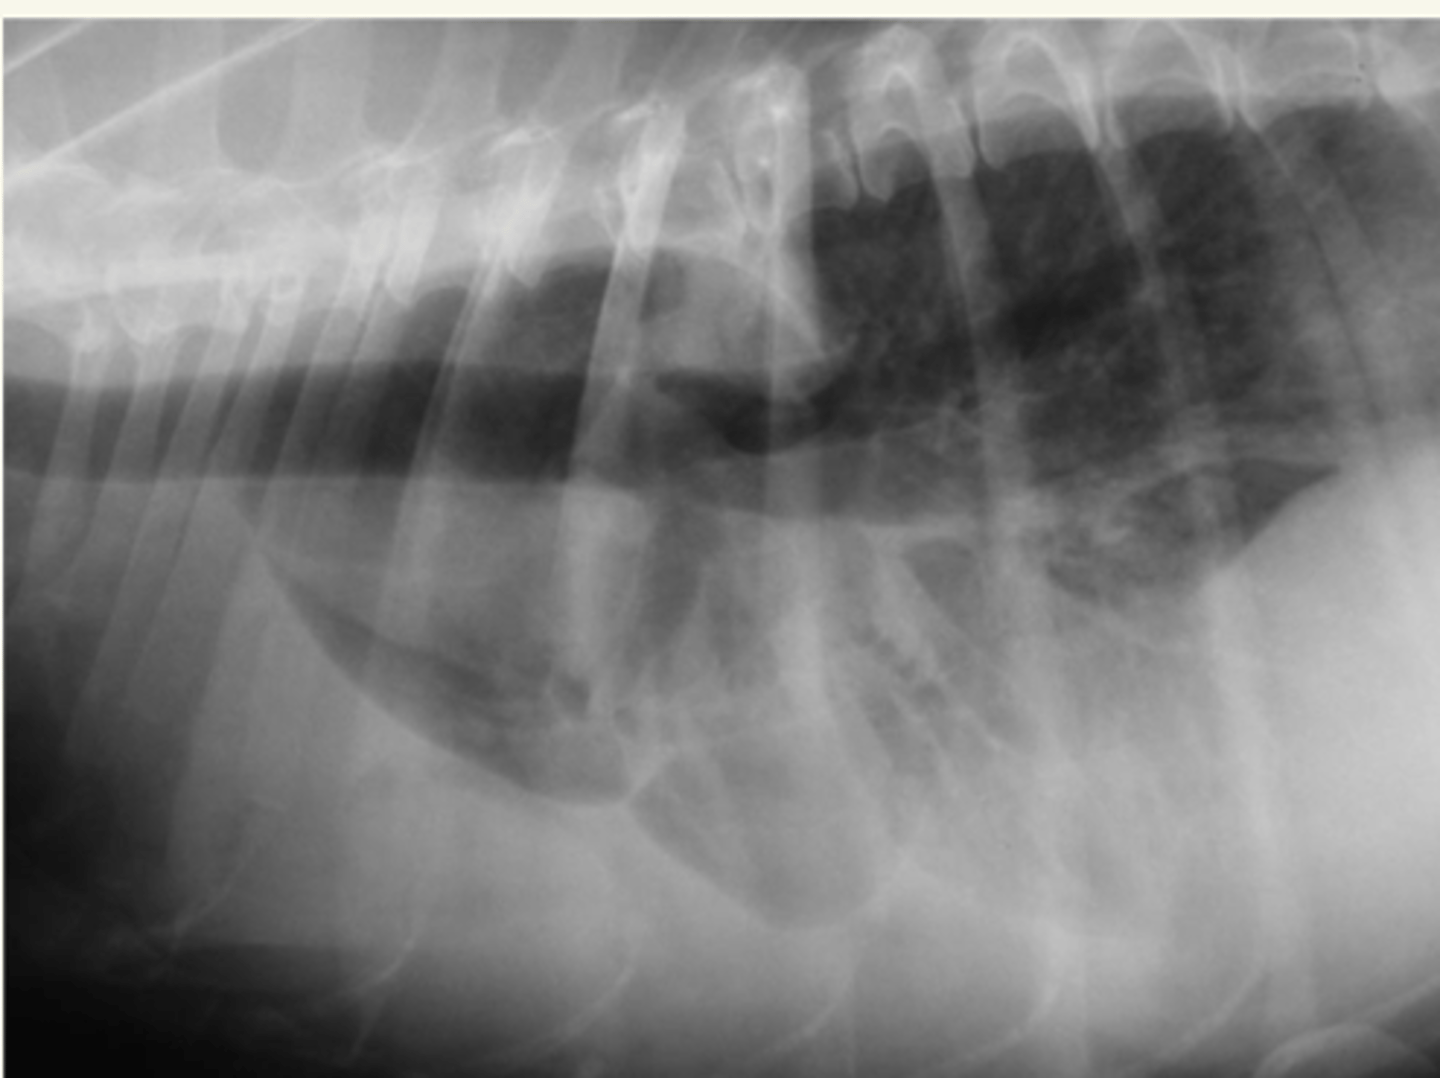

edema pulmonar

patología: